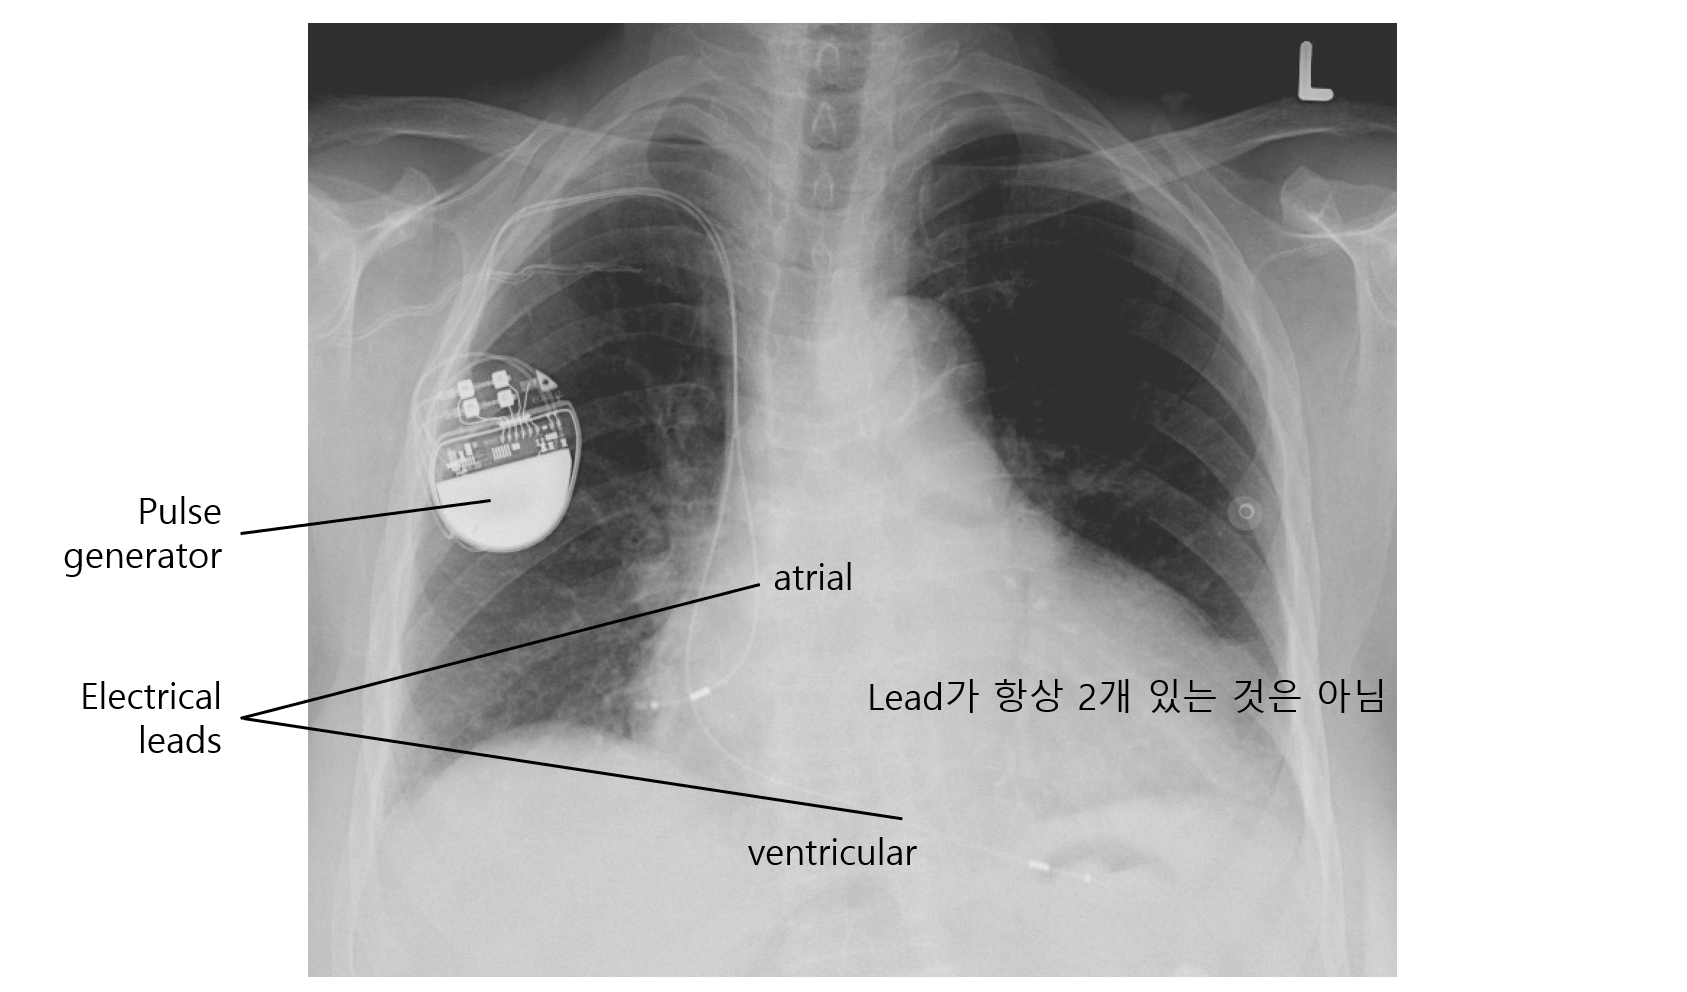

(1) 구성요소

① Pulse generator: Lead가 보내준 전기 신호를 해석하고, lead로 전기 신호를 보냄

② Electrical lead: 심근의 전기 신호의 유무, 간격, 기간 등을 감지하고, pulse generator의 전기 신호를 전달

• Lead는 pacemaker의 mode(아래 참고)에 따라 1개일 수도, 2개일 수도 있음